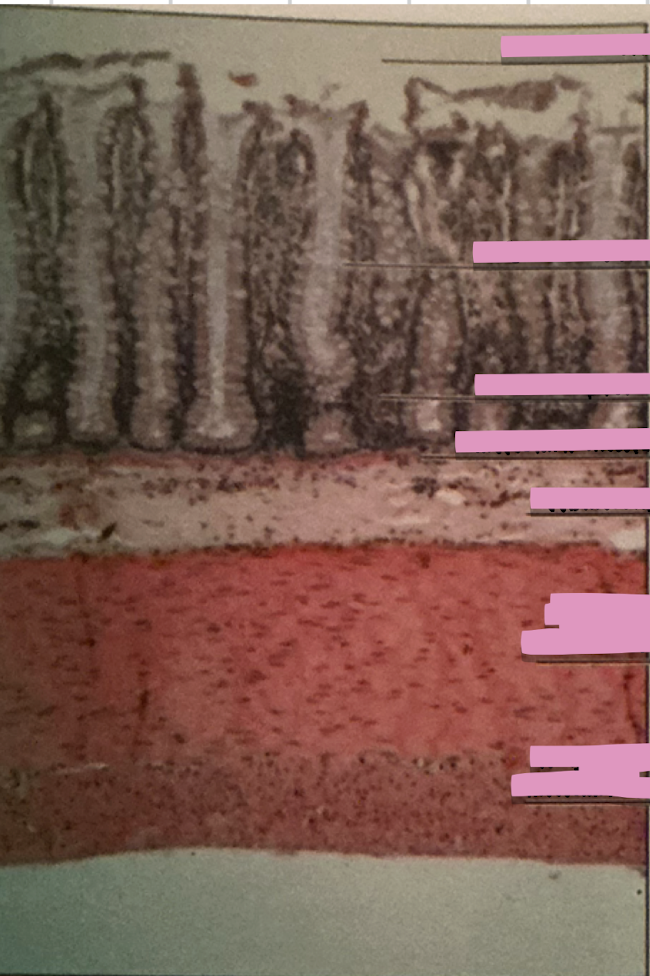

duodenum

brunner’s glands

intestinal epithelium

duodenum

________ receives chyme when stomach empties; exocrine release site for gallbladder & pancreatic secretions

intestinal glands

secrete mix of sucrase, maltase, & peptidases + definsins & enzymes

brunner’s glands

produce mucus-rich alkaline secretion to protect from acidic content, lubricate walls, & enable absorption

goblet cells

single-celled exocrine glands secrete mucus